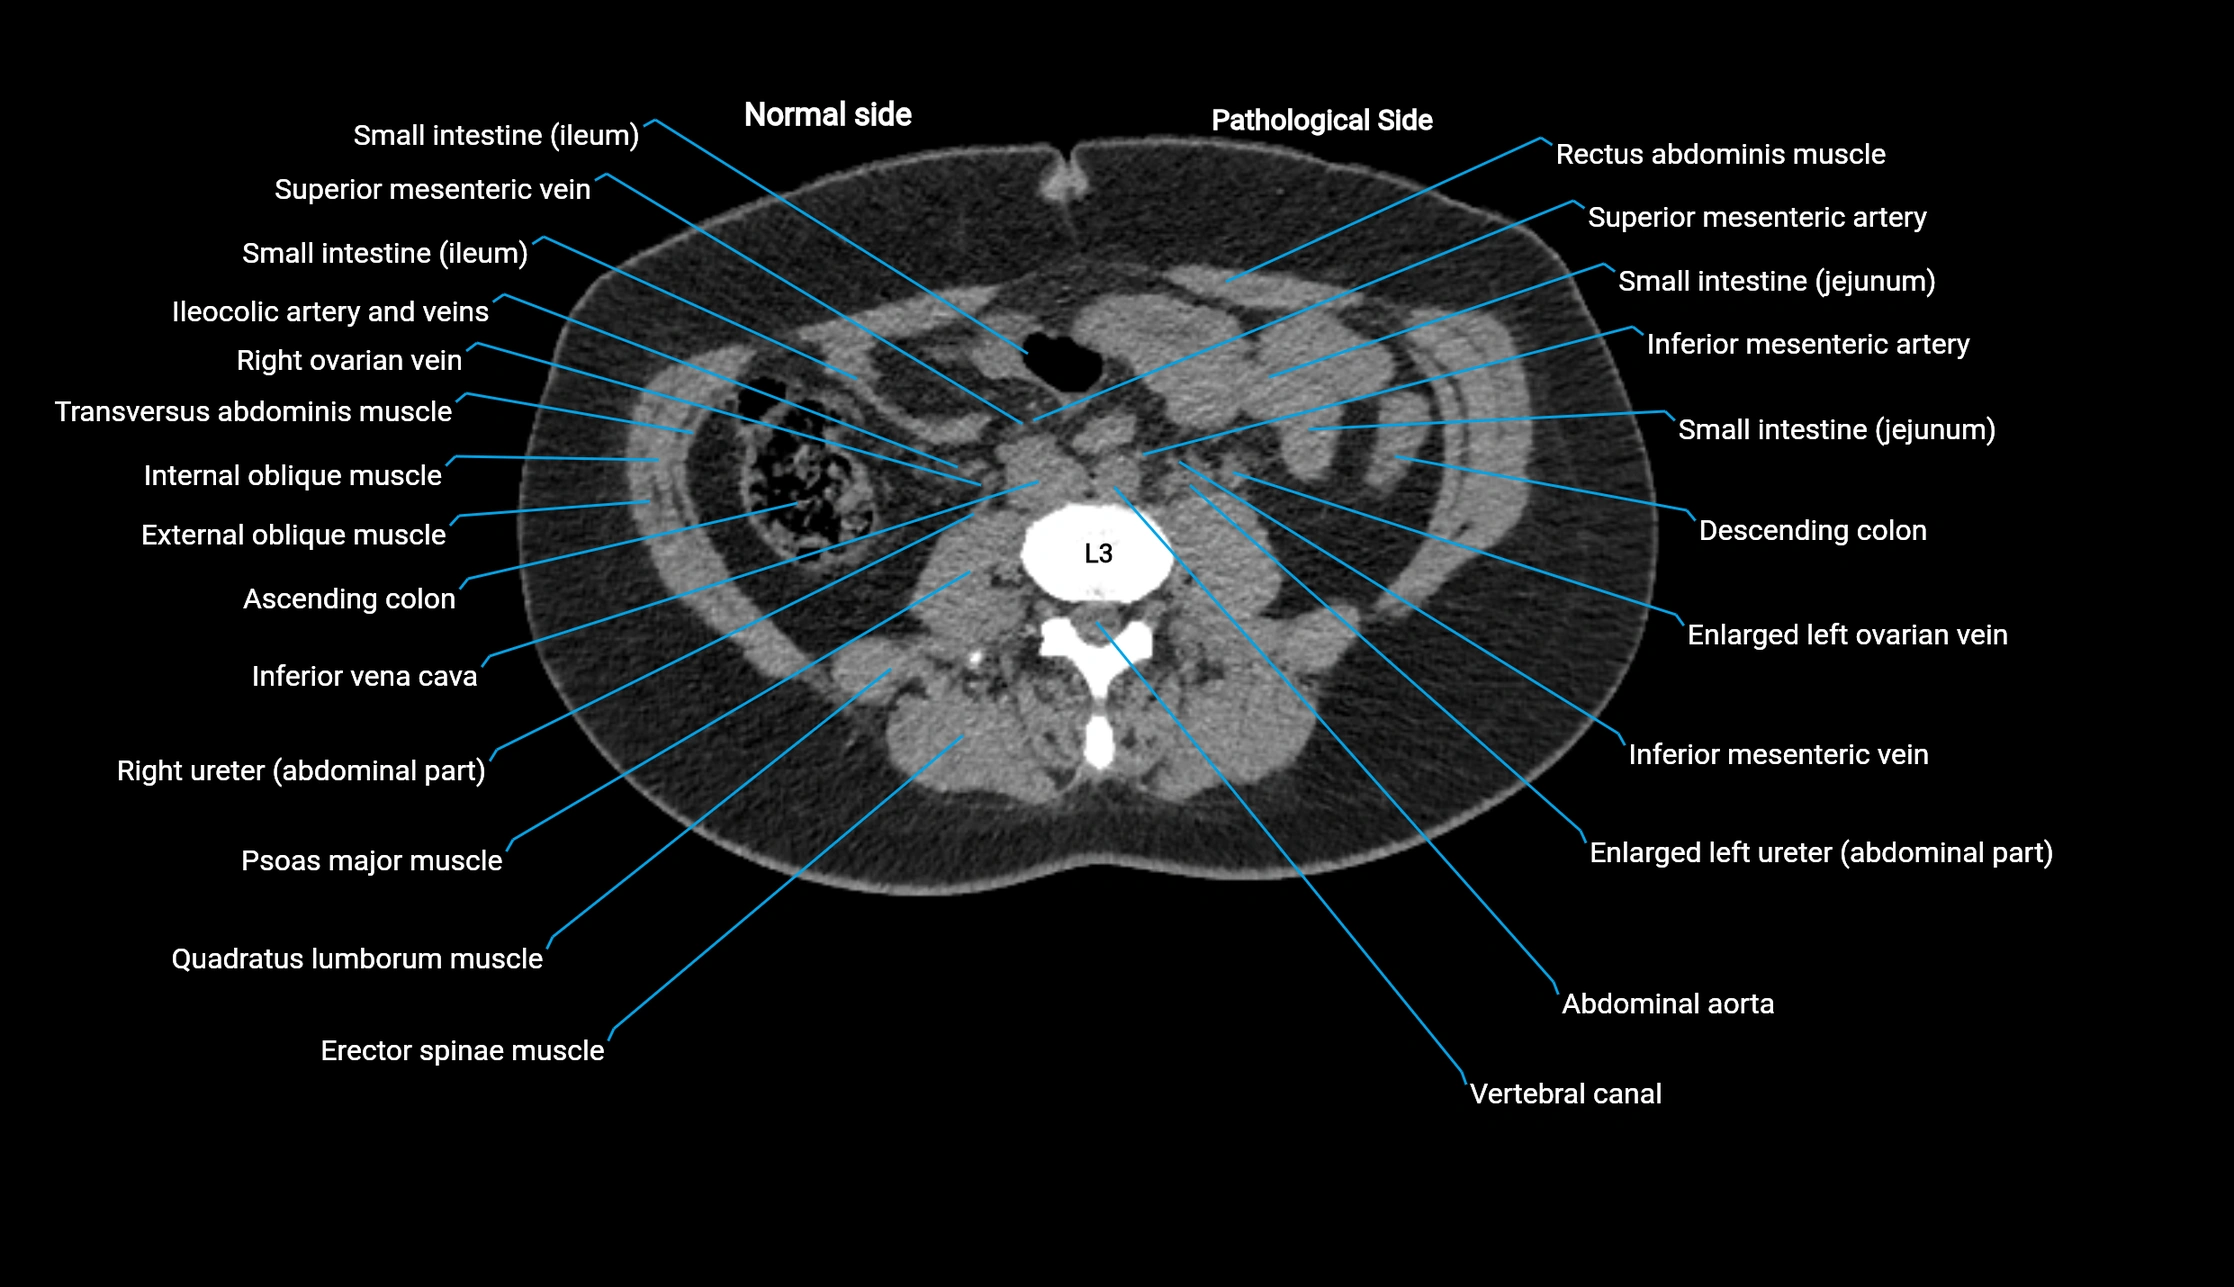

CT image

image